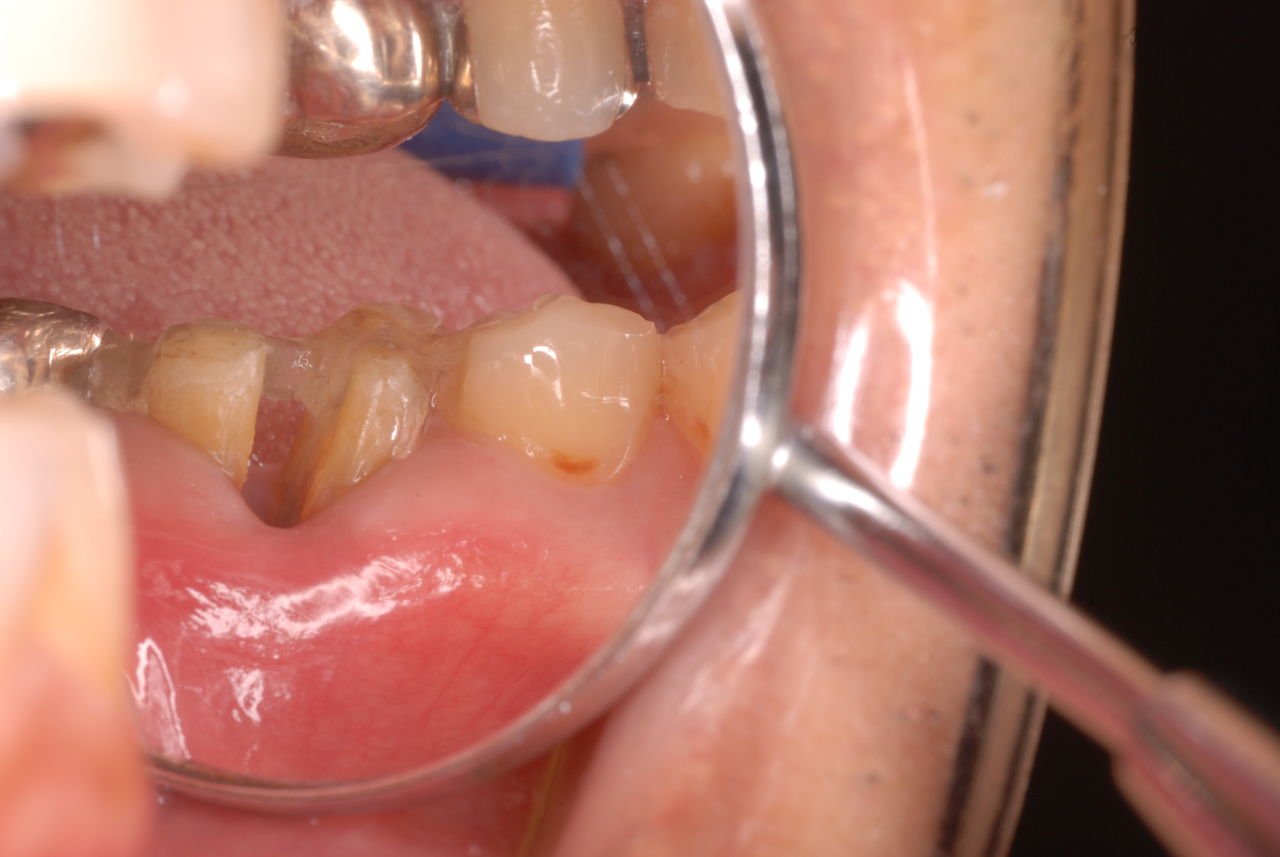

他の都心の矯正歯科で治療中で、ほぼ終了近くの方でした。歯並びで言えば上下の歯が突出していて唇が閉じにくいというのをなんとかしたい。そして歯を抜かないで出来るところを探して都心の矯正歯科への通院となりました。ところが本人曰くよく噛めないというのです。

相談しても“問題無い”の説明だけだそうです。調べたところ歯周病は進行しているし、奥歯の大きい歯2本ずつ計4本はしっかり噛んでいないのです。よく噛めないというのはそのことのようでした。これを矯正的に元に戻すことはできない訳ではありませんが、時間と手間がかかるのは間違いないことです。

歯を削らないといいましても結局歯の間を削りスペースを確保したそうですから、何らかの歯に対する傷害はしているのです。それは虫歯や歯周病を起こしやすい理由にもなりますからこれからも要注意なのです。二年間という貴重な時間を費やしていますから患者本人は大変だったと思います。そして二年間を要したならば更に二年間動かないようにするための入れ歯やマウスピースを装着し続けなければいけないのです。